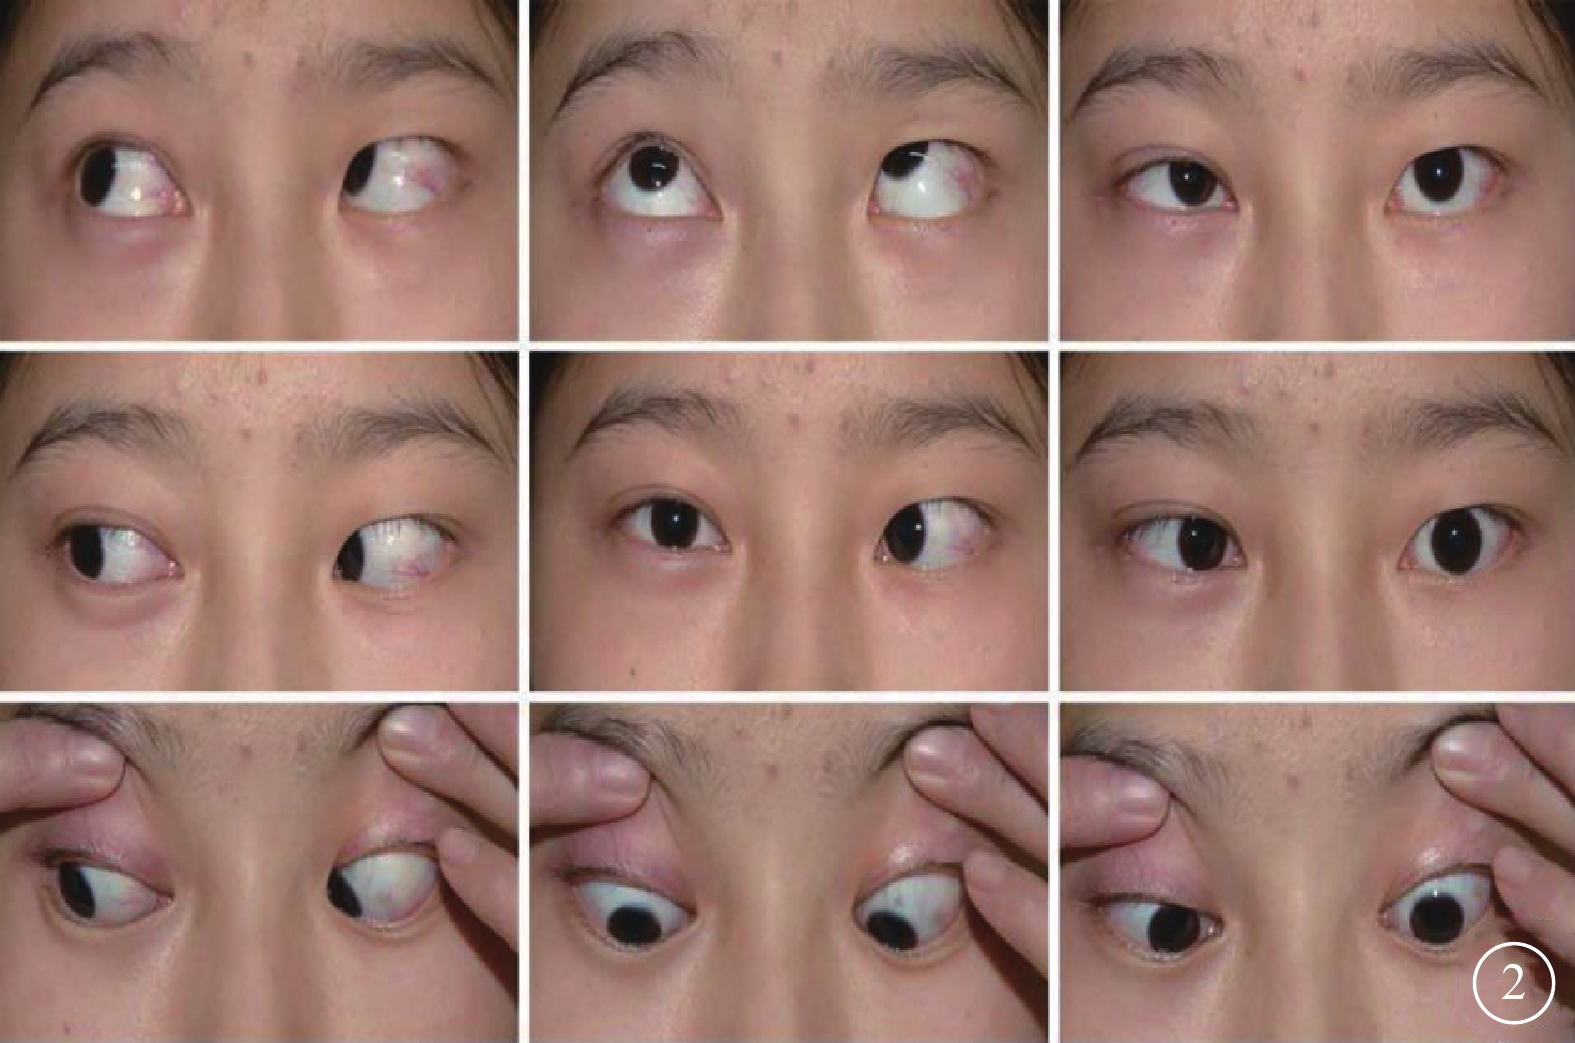

患者女,18歲。2010年9月因頭枕部外傷致意識喪失入院。醒后發現左眼內斜、眼球運動障礙、視力下降伴口角右偏。眼眶CT檢查未見異常;頭顱MRI檢查顯示小腦蚓部出血致雙側小腦半球、第四腦室及背側腦橋受壓變形(圖1)。傷后10 d行顱內血腫清除手術。手術后上述癥狀無改善且逐漸出現左眼瞼閉合不全、視力逐漸下降。為求進一步診治于2015年12月到我科就診。否認既往眼病及全身病史。眼部檢查:右眼視力1.0;左眼視力0.1,不能矯正。雙眼瞳孔等大,對光反射靈敏;左眼相對性瞳孔傳入性障礙(+)。雙眼視盤邊界清楚,顏色淡,以左眼為著;黃斑中心凹反光清晰。雙眼眼壓正常。視野檢查,右眼生理盲點擴大,鼻下象限視野部分缺損,視敏度下降;左眼顳側及鼻上象限視野不規則缺損。光相干斷層掃描檢查,雙眼視盤周圍視網膜神經纖維層變薄。眼位檢查,右眼注視時左眼內斜約30°;左眼注視不良。眼球運動檢查,右眼外展正常伴輕度水平眼球震顫,內收受限,鼻側角膜緣僅到達上、下淚小點連線;左眼外展受限,顳側角膜緣剛過中線,內收正常(圖2),單眼和雙眼運動相同;輻輳反射正常。神經系統檢查,左側額紋消失,瞼裂閉合不全,鼻唇溝變淺,舌前2/3味覺減退;口角向右偏斜,鼓腮時左側漏氣。診斷:(1)麻痹性內斜視;(2)非典型性八個半綜合征;(3)外傷性視交叉病變;(4)雙眼視神經萎縮。行左眼上、下直肌1/2轉位聯合內直肌后退手術。手術后眼位正,隨訪半年眼位穩定。

眼位及眼球運動檢查圖。左眼內斜,外轉受限;右眼內轉輕度受限

眼位及眼球運動檢查圖。左眼內斜,外轉受限;右眼內轉輕度受限

患者女,18歲。2010年9月因頭枕部外傷致意識喪失入院。醒后發現左眼內斜、眼球運動障礙、視力下降伴口角右偏。眼眶CT檢查未見異常;頭顱MRI檢查顯示小腦蚓部出血致雙側小腦半球、第四腦室及背側腦橋受壓變形(圖1)。傷后10 d行顱內血腫清除手術。手術后上述癥狀無改善且逐漸出現左眼瞼閉合不全、視力逐漸下降。為求進一步診治于2015年12月到我科就診。否認既往眼病及全身病史。眼部檢查:右眼視力1.0;左眼視力0.1,不能矯正。雙眼瞳孔等大,對光反射靈敏;左眼相對性瞳孔傳入性障礙(+)。雙眼視盤邊界清楚,顏色淡,以左眼為著;黃斑中心凹反光清晰。雙眼眼壓正常。視野檢查,右眼生理盲點擴大,鼻下象限視野部分缺損,視敏度下降;左眼顳側及鼻上象限視野不規則缺損。光相干斷層掃描檢查,雙眼視盤周圍視網膜神經纖維層變薄。眼位檢查,右眼注視時左眼內斜約30°;左眼注視不良。眼球運動檢查,右眼外展正常伴輕度水平眼球震顫,內收受限,鼻側角膜緣僅到達上、下淚小點連線;左眼外展受限,顳側角膜緣剛過中線,內收正常(圖2),單眼和雙眼運動相同;輻輳反射正常。神經系統檢查,左側額紋消失,瞼裂閉合不全,鼻唇溝變淺,舌前2/3味覺減退;口角向右偏斜,鼓腮時左側漏氣。診斷:(1)麻痹性內斜視;(2)非典型性八個半綜合征;(3)外傷性視交叉病變;(4)雙眼視神經萎縮。行左眼上、下直肌1/2轉位聯合內直肌后退手術。手術后眼位正,隨訪半年眼位穩定。

眼位及眼球運動檢查圖。左眼內斜,外轉受限;右眼內轉輕度受限

眼位及眼球運動檢查圖。左眼內斜,外轉受限;右眼內轉輕度受限